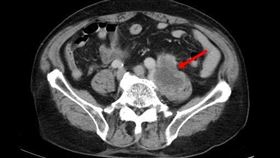

棄正規治療 腸癌男腫瘤衝破肛門丟命

一名罹患直腸癌二期的范姓患者,因為接受許姓醫師的治療...

2017/05/23 16:48